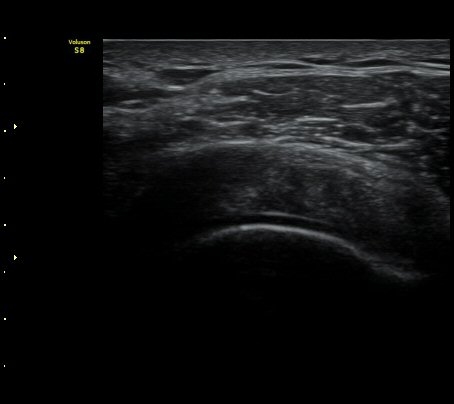

±Ø»ó°Ç Ⱦ´Ü¸é°Ë»ç½Ã ±Ø»ó°Ç ÀϺΠÀú¿¡ÄÚ ºÎÁ¾°ú ¹Ì¼¼ÇÑ °Ç ¿¬°á¼º ¼Ò½ÇÀÌ °üÂûµÊ(±×¸² 4, 5).

±×¸² 4)¿¡¼­ °üÀý¿¬°ñ°æ°è¸é ¡ÈÄ(articular interface sign)°¡ °üÂûµÊ.